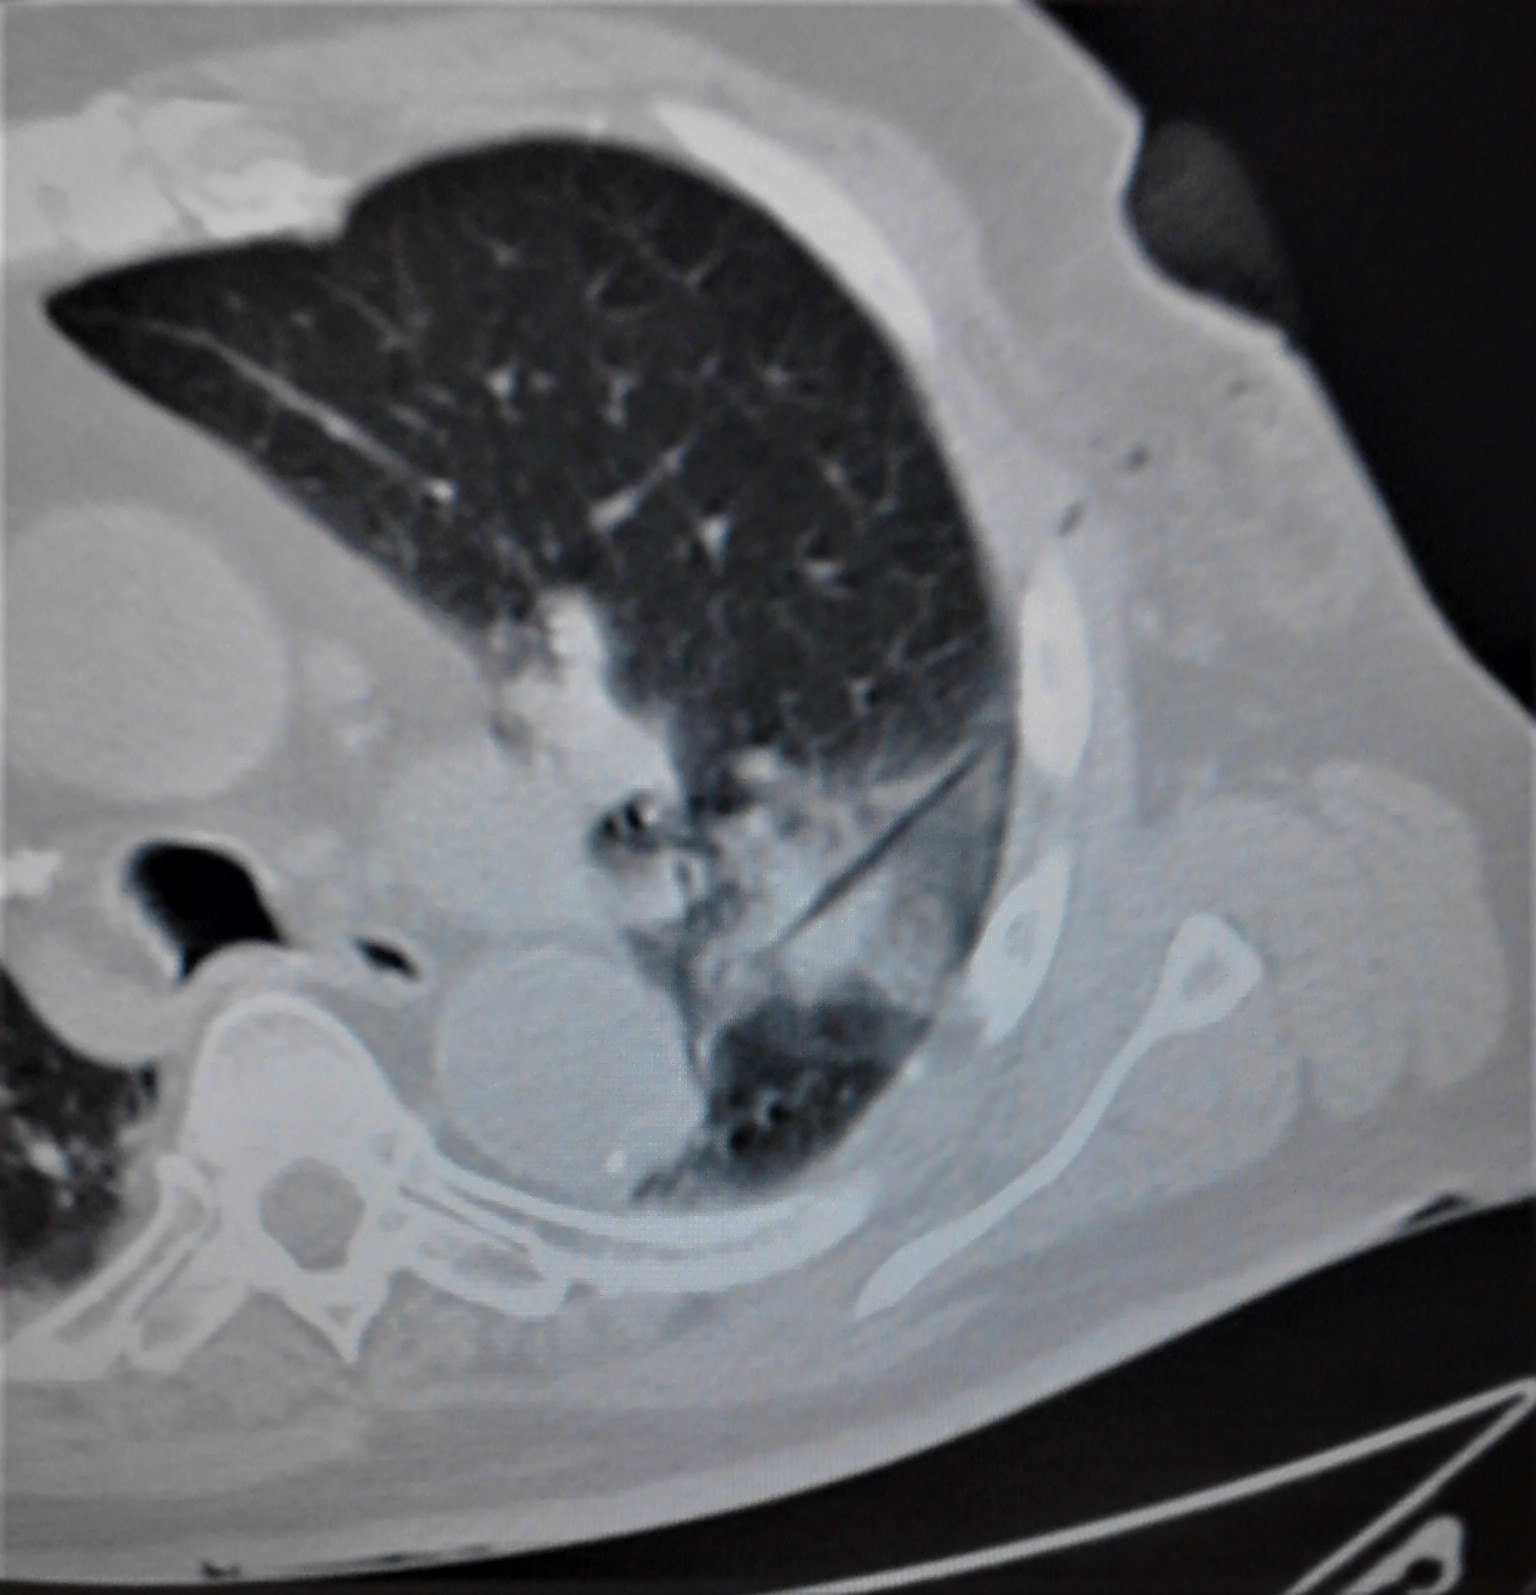

The doctors apply microwave energy to destroy tumors located both centrally and peripherally within the lung using computer tomography (CT) image guidance. The tumors include colorectal cancer, lung adenocarcinoma, thymoma, uterine leiomyosarcoma and ampullary carcinoma in origination. Microwave energy applicators are introduced into the tumors in the lung percutaneously, a minimally invasive technique. A small hole is made through the skin near the tumor location and an applicator is inserted into the lung cavity and lung towards the tumor. Once the positioning of the antenna with respect to the tumor is verified with CT image guidance, microwave energy is applied to the antenna in contact with the tumor to destroy it. The procedures usually take an hour or two depending on the complexity of tumor location and shape to achieve good antenna positioning. The microwave energy application is controlled with direct temperature feedback from the ablation antenna during the procedure to ensure safety and efficacy. Temperature feedback control prevents overheating and runaway conditions and thereby provides the extra safety net for the patients and procedures.

AveCure® microwave ablation system is successfully treating tumors in the lung using a minimally invasive technique. The microwave ablation antenna is introduced through a percutaneous chest wall incision in the skin to access the tumor past the lung cavity and patient is left with a small hole in the skin which quickly heals with almost no scar after the procedure. AveCure® system utilizes a smart antenna in either probe or catheter format and microwave energy controller to select the correct size, temperature and timer settings appropriate for safe, effective and predictable treatment.